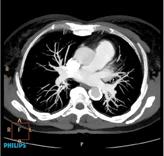

CTA is one of the most complex procedures routinely performed on a CT scanner. A successful CTA exam requires synchronization of the timing of the scan with maximum vessel contrast enhancement.

Several factors influence vessel enhancement. Some are patient-related, such as weight and cardiac output, while others are related to contrast, such as concentration and injection rate. It is well established that maximum vessel enhancement benefits from optimal contrast volume, injection rate, and contrast concentration. Modifying injection protocols for various patient populations can be quite challenging.

Bolus tracking — BolusPro software on Philips Ingenuity CT allows the user to synchronize the start of the scan with predefined vessel enhancement. The user can place a region of interest on a vessel and define a Hounsfield unit threshold. Reaching a predefined threshold for vessel enhancement triggers the start of CT scanning.